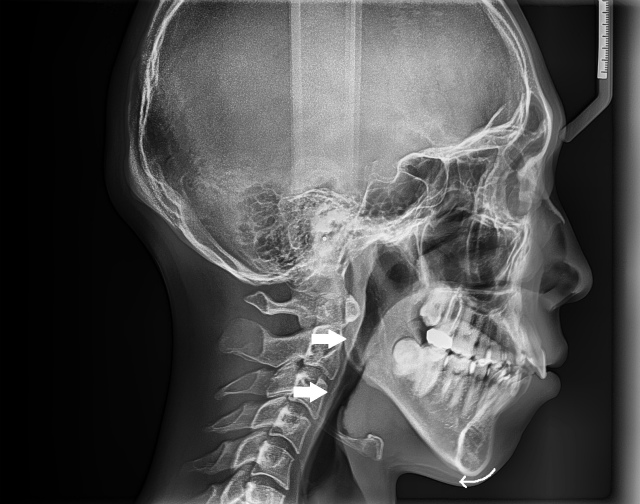

一番上の矢印は咽頭扁桃(アデノイド)が腫れている箇所を示している。気道が全域で狭くなっている (8歳男児)